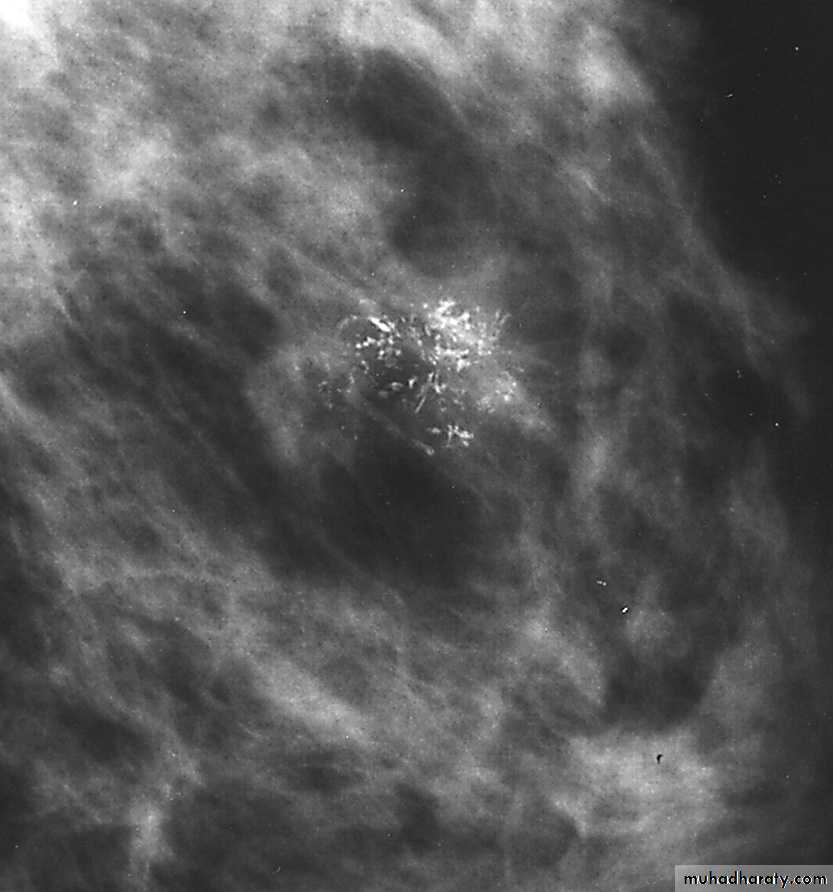

Malignant microcalcification